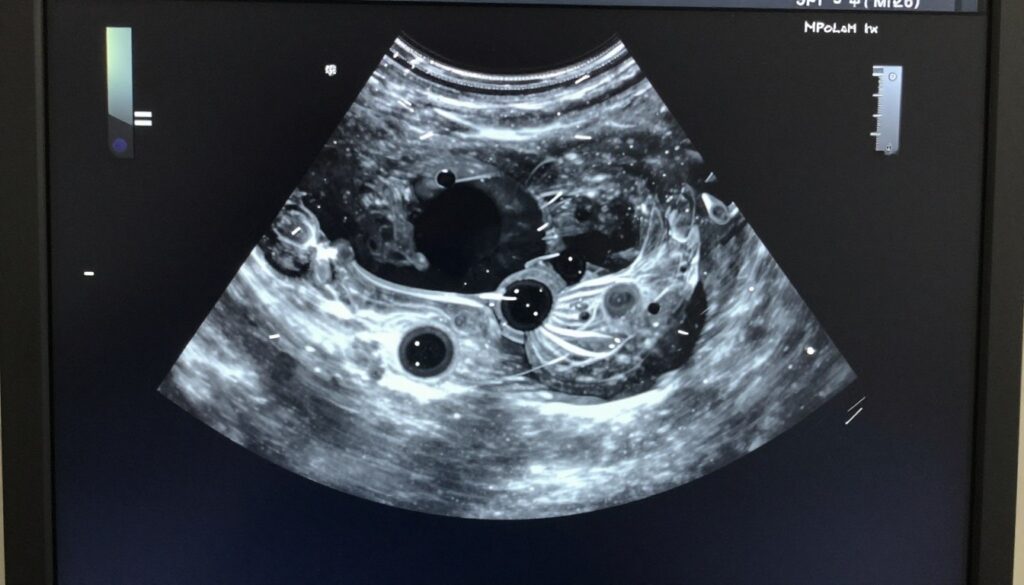

Transvaginal ultrasound provides detailed views of reproductive organs. This procedure uses a probe inserted into the vagina. Sound waves create images of the uterus and ovaries. Antral follicle count occurs during early cycle baseline ultrasounds. Small follicles visible on the ovaries predict how many eggs might develop during stimulation.

Ultrasound evaluates uterine structure and identifies abnormalities. Fibroids appear as solid masses in or around the uterus. Polyps project into the uterine cavity. Both conditions may interfere with implantation. Ultrasound measures uterine lining thickness. Adequate thickness is necessary for embryo implantation. Ovarian cysts or masses are also visible on ultrasound.

Polycystic ovary syndrome is the most common hormonal disorder in reproductive-age women. The condition involves irregular ovulation or anovulation. Women with PCOS often have irregular or absent periods. Ovaries contain multiple small follicles visible on ultrasound. These follicles don’t mature and ovulate normally. Hormone imbalances include elevated androgens.

Diminished ovarian reserve means fewer eggs remain in the ovaries. Age is the primary cause. Egg quantity declines throughout life. Quality also deteriorates with age. Some women experience premature decline. Genetic factors, surgeries, or treatments may damage ovaries. Testing reveals low AMH and elevated FSH levels. Antral follicle count is reduced on ultrasound.